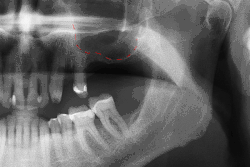

Panorex radiograph showing implants

Xray of four Straumann implants and abutments